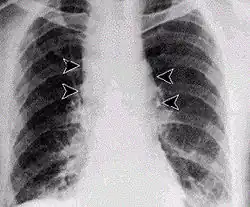

Inhalational anthrax, mediastinal widening

It infects the lymph nodes in the chest first, rather than the lungs themselves, a condition called hemorrhagic mediastinitis, causing bloody fluid to accumulate in the chest cavity, thereby causing shortness of breath. The second (pneumonia) stage occurs when the infection spreads from the lymph nodes to the lungs. Symptoms of the second stage develop suddenly within hours or days after the first stage. Symptoms include high fever, extreme shortness of breath, shock, and rapid death within 48 hours in fatal cases.[29]